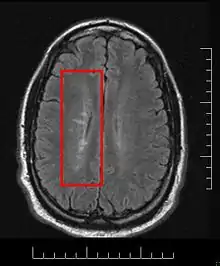

This morphologic appearance was named Dawson's fingers by Charles Lumsden, after the Scottish pathologist James Walker Dawson,[31] who first defined the condition in 1916.

Dawson's fingers

"Dawson's fingers" is the name for the lesions around the ventricle-based brain veins[32][33] of patients with multiple sclerosis and antiMOG associated encephalomyelitis[34]

Though once thought to be specific of MS, it is known not to be the case.[35]

The condition is thought to be the result of inflammation or mechanical damage by blood pressure[30] around long axis of medular veins.

Dawson's fingers spread along, and from, large periventricular collecting veins, and are attributed to perivenular inflammation.[36]

Lesions far away from these veins are known as Steiner's splashes.[30]